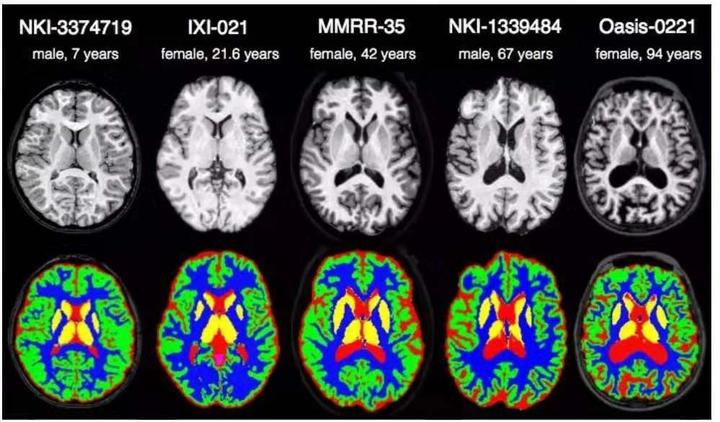

机器学习模型

机器学习模型

无需编程经验即可使用的机器学习工具,支持分类、回归、聚类等常见机器学习任务。

医学影像处理与分析工具,支持图像分割、特征提取和量化分析,辅助临床诊断。